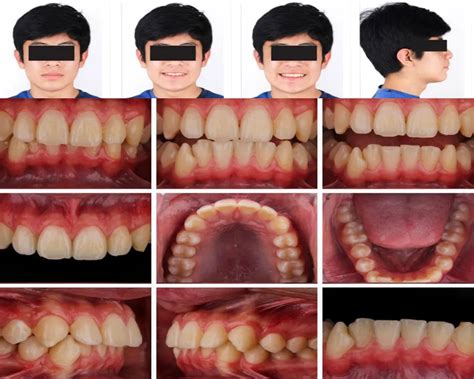

Figura 1 Fotografías extraorales pretratamiento.

Se trata de una paciente de aspecto mesocefálico, sin asimetrías evidentes, salvo una ligera desviación de la pirámide nasal hacia la derecha, con tercios faciales proporcionados, labios competentes y presencia de un hábito de interposición labial. En sonrisa, observamos una correcta exposición vertical gingival, la línea media dentaria superior está centrada con respecto a la línea media facial y se adivina un maxilar comprimido. En el perfil, los tercios faciales aparecen proporcionados, con un ángulo nasolabial obtuso y un ángulo mentolabial muy marcado. Nos llama la atención la falta de protagonismo de la mandíbula en el perfil facial, que es ligeramente convexo (fig. 1).

Figura 2 Fotografías intraorales pretratamiento.

Figura 3 Fotografías intraorales pretratamiento. Vista oclusal.

La paciente ya ha iniciado la segunda fase de recambio de la dentición mixta, existiendo caries oclusodistal en 64, origen de un absceso que fistuliza a este nivel por vestibular, posible caries palatina en 26 y oclusomesial a nivel de 74. Ambos primeros molares superiores presentan sendas obturaciones oclusales. La relación molar es de Clase II, completa en el lado derecho e incompleta en el lado izquierdo, estando aumentados el resalte y la sobremordida. La oclusión en relación céntrica mandibular es coincidente con la máxima intercuspidación. Existe una ligera discrepancia de líneas medias, estando la línea media inferior levemente desplazada hacia la derecha con respecto a la superior. Los incisivos superiores aparecen diastemados, intuyéndose una discrepancia oseodentaria positiva en la arcada superior, mientras que, por el contrario, la arcada inferior evidencia una clara discrepancia oseodentaria negativa (figs. 2 y 3).